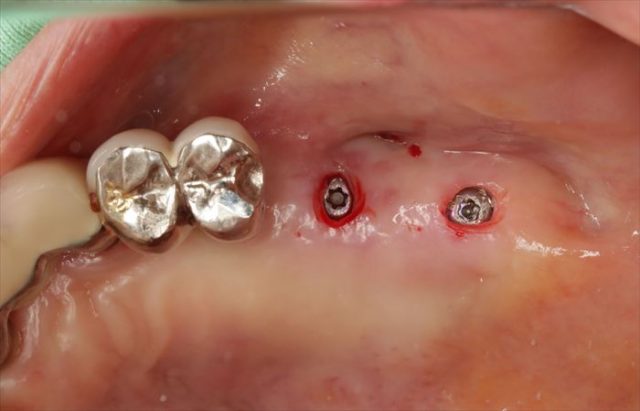

インプラント埋入を終えました。

頬側面観です。

挿入ジグを外しました。

封鎖スクリューで封鎖してインプラントオペの終了です。

出血も最小限で済み、縫合しないため抜糸が不要です。